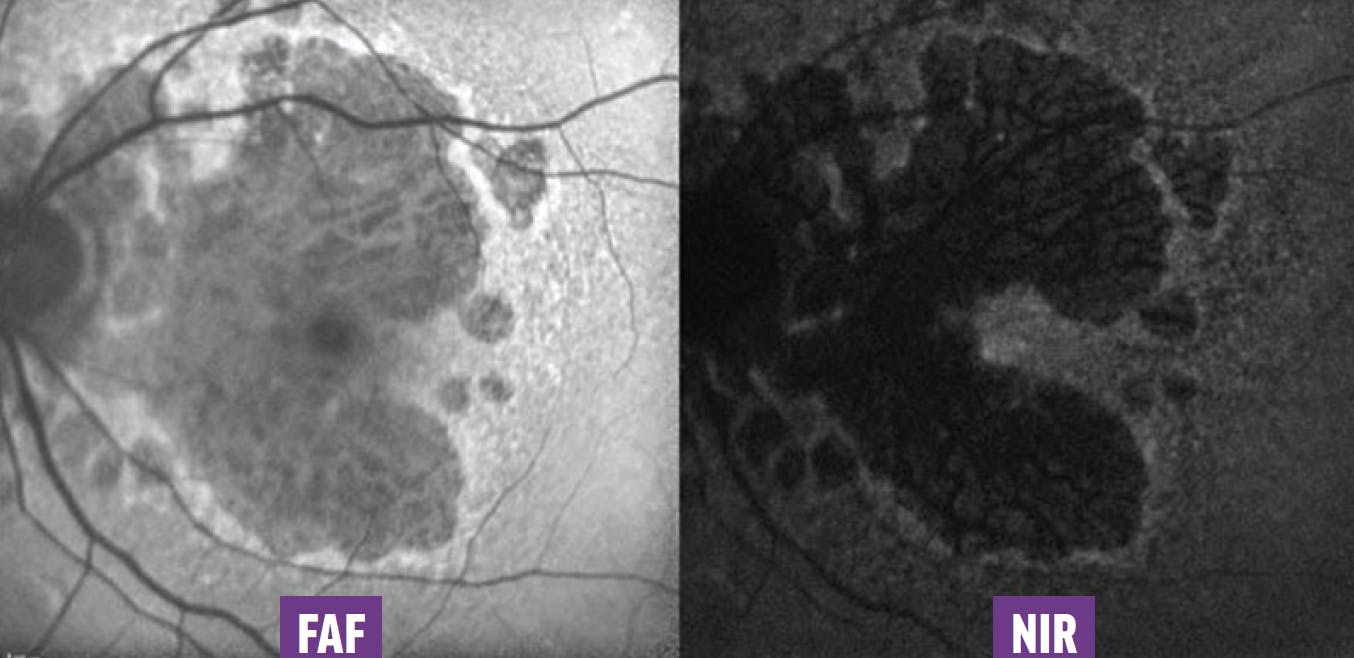

Near-infrared reflectance (NIR) imaging (between 800 nm and 2,500 nm) penetrates deeper than FAF (between 420 nm and 500 nm) through the different layers of the retina. Thus, the combination of NIR and FAF images allows a more detailed assessment of fovea-sparing lesions (Figure 3).6

<p>Figure 3. Because of the xanthophyll pigment, the foveal zone appears dark on FAF imaging, while the foveal sparing is more obvious on NIR imaging.</p>

Figure 3. Because of the xanthophyll pigment, the foveal zone appears dark on FAF imaging, while the foveal sparing is more obvious on NIR imaging.